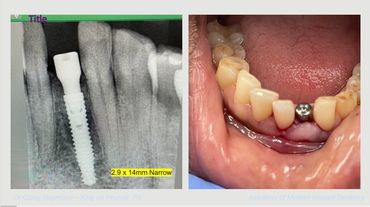

Where and how to use 2.9 Narrow implant